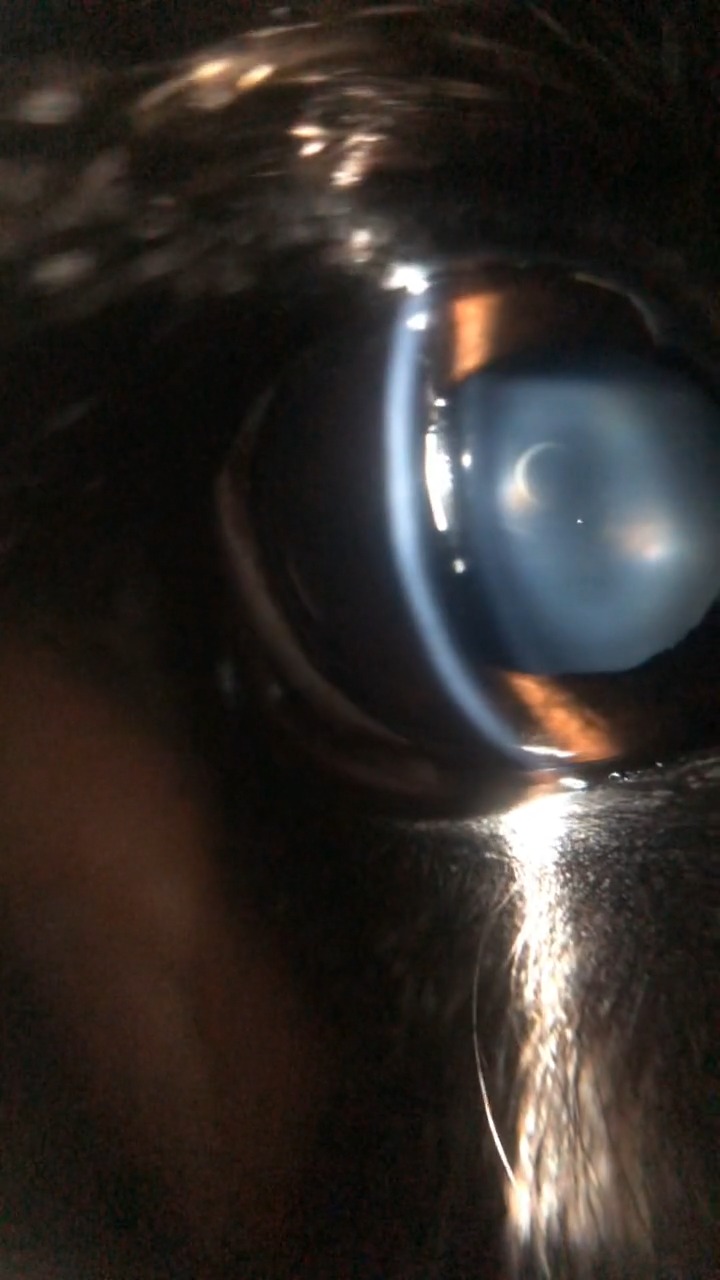

水晶体

水晶体脱臼・核硬化性・白内障(発症部位・進行度評価)

スリットランプ、青色拡散光、白色拡散光により前眼部の診断が可能になります。

Smart Eye Camera で診察可能な疾患例